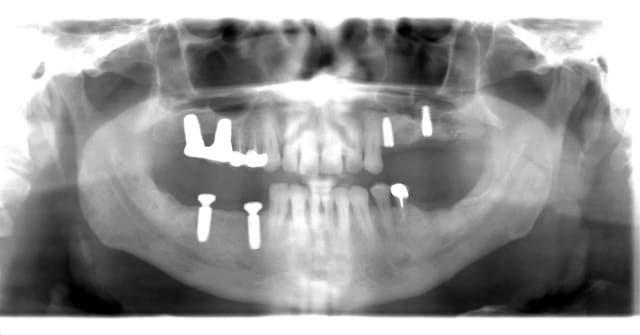

Voila je me lance, mais je n'ai que les RX.

24: largeur de crete 3mm, hauteur 9.8, j'ai placé un 3.75x10

26: largeur de crete 4mm, hauteur 4.7, j'ai placé un 4.2x7

A vos critiques et au plaisir de vous lire.

si oui, fais attention, çà déforme un peu les perspectives...donc peut fausser ton axe de forage (cf ton implant en 24 qui "louche" vers la 23...)